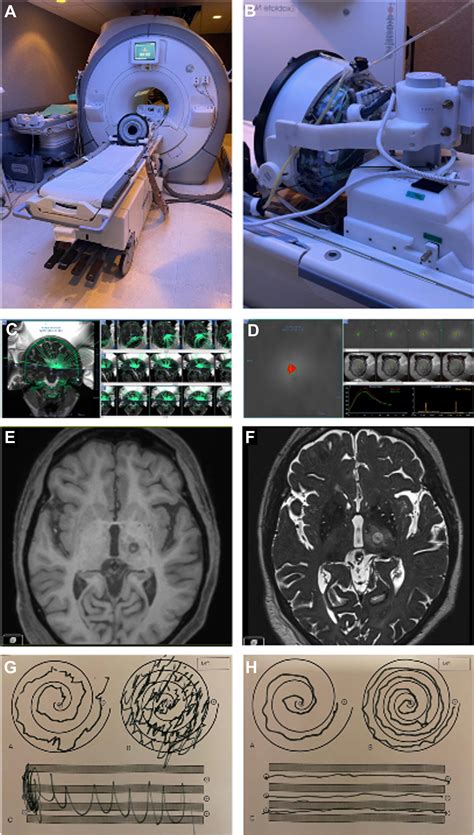

My new back hardware (ALIF neurosurgery) : r/Radiology